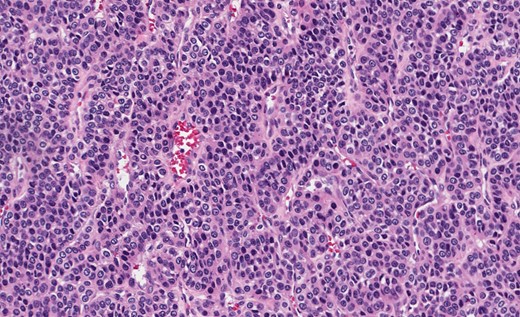

Grossly, GTs are multinodular, soft and rubbery on sectioning [3]. The cellular nodules are separated by streaks of gastric smooth muscle, which also surrounds the tumor [3]. Histologic features are central round to oval nuclei with inconspicuous nucleoli and clear to eosinophilic cytoplasm with distinct cell borders [1] (Figs. 3 and 4). GTs are positive for α-smooth muscle actin, vimentin, calponin and caldesmon. They are most often negative for CD117, CD34, chromogranin and synaptophysin [3, 6].

Gastric GT. Note central round or oval nuclei with clear, eosinophilic cytoplasm (H&E stain, ×200).